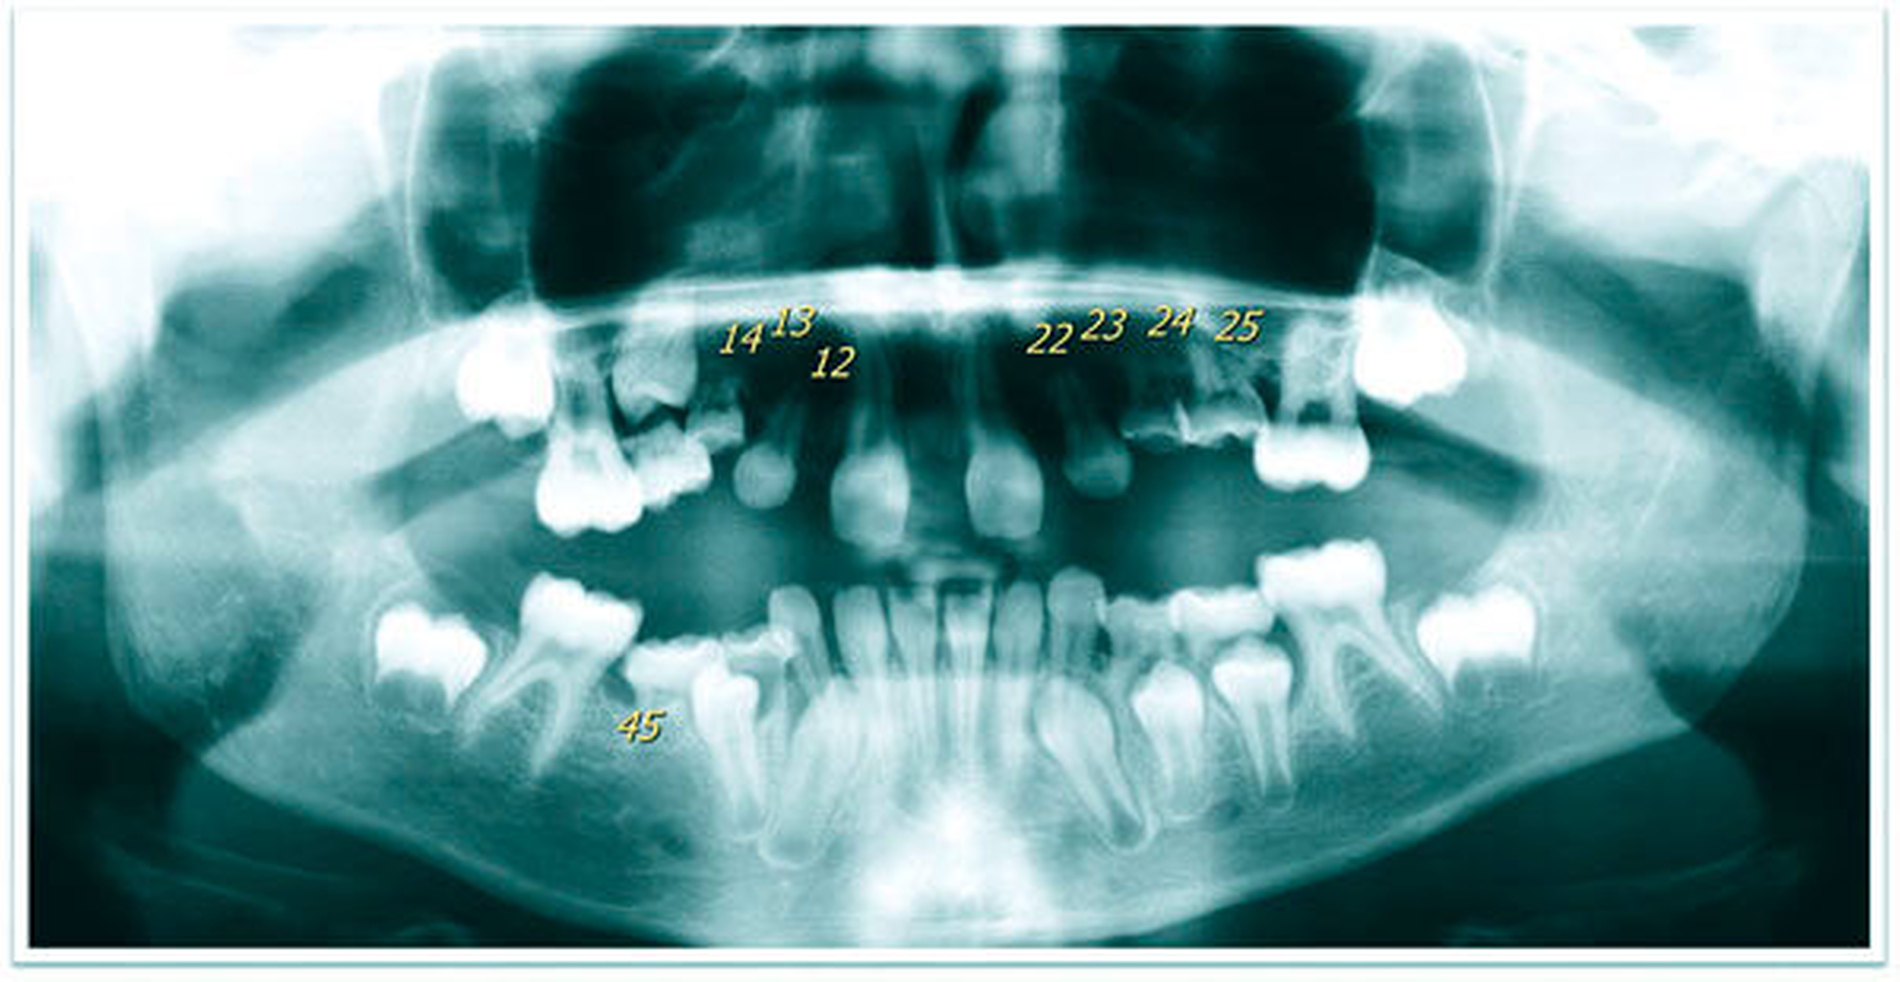

Die zehnjährige Patientin wurde uns von der Kieferorthopädin zur Wertung möglicher chirurgischer Maßnahmen bei insgesamt acht Nichtanlagen (Abbildung 1a bis c) vorgestellt. Im OPG stellt sich das Fehlen von drei permanenten Zähnen im I. Quadranten, von vier im II. Quadranten und einem im III. Quadranten dar (Abbildung 1c). Aufgrund des noch jungen Alters der Patientin zum Zeitpunkt der Erstvorstellung und des damit noch verbundenen Vorhandenseins der Milcheckzähne 73 und 83 entschieden wir uns für das folgende kieferorthopädisch-kieferchirurgische Vorgehen (Abbildung 2):

1. Schließen des Diastemas durch KFO zur Schaffung von Platz für Transplantate in regio 12 und 22,

2. Extraktion der ankylosierten und in Infraposition stehenden Milchmolaren 55, 54, 64, 65, 75, 74, 84 und 85,

3. Autogene Transplantation der unteren Milcheckzähne 73 und 83 in die vorher geschaffenen Lücken in Position 12 und 22 (Abbildungen 3a, b) sowie

4. Ausgleichstransplantation des Zahns 35 in Position 24 mit dem Ziel einer gleichmäßigen Verteilung von jeweils einem Prämolaren pro Quadranten (Abbildung 3b).